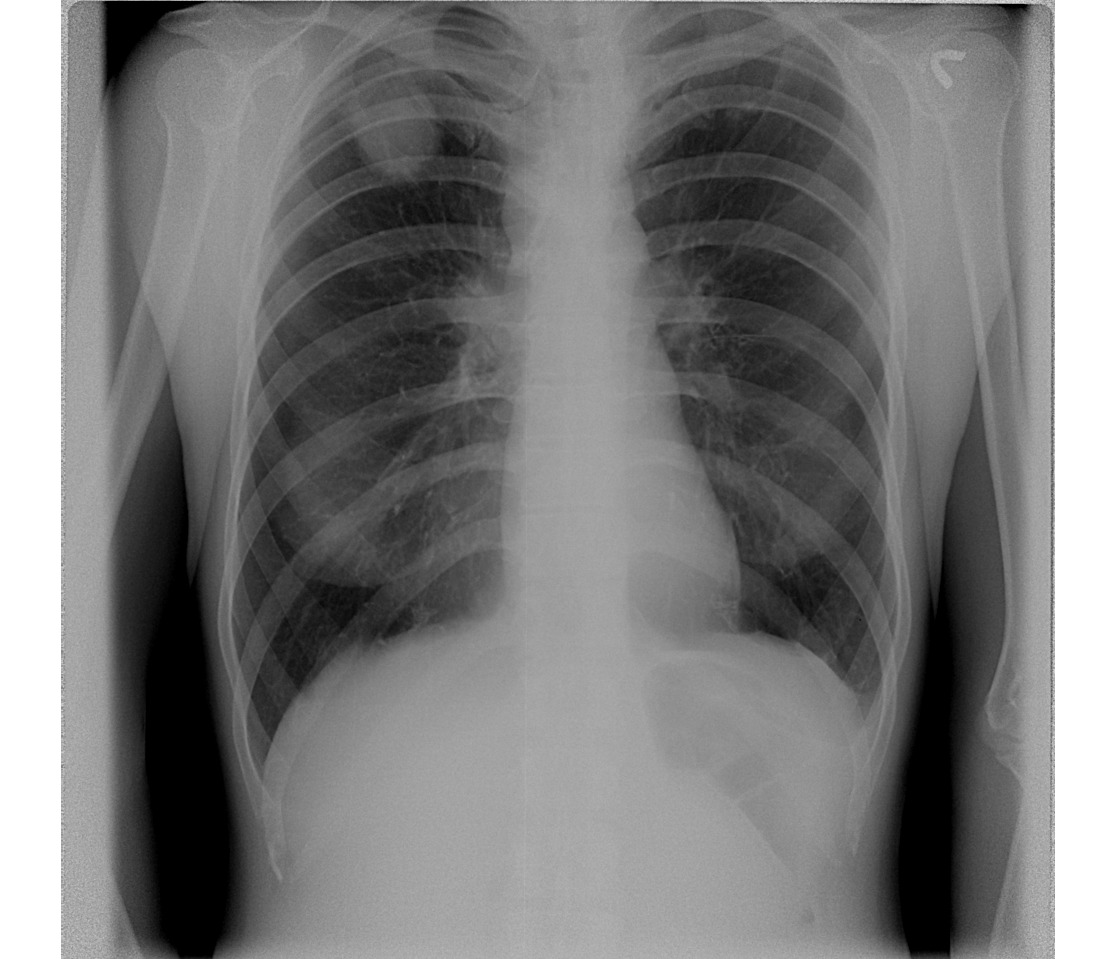

случай 1. Ж, 51 год, увеличение надключичных л/у слева (до 4 см), подмышечных слева. Врачи предполагают метастазирование, ищут превичную опухоль. Где кругляк на боковом? я не вижу.. Легочных жалоб нет.

По первому случаю, кроме округлой тени справа, вижу группы очаговых теней слева. О туберкулёзе думаю

Я их вижу больше,чем нарисовано выше,думаю,метастазы-круглые,ровные,без распада.Во втором случае не померещилось,тень есть.

Да,наверху больше.Но локализация-это еще не всё.Кстати,слева и внизу есть,сейчас не могу обрисовать.

Могу по первому случаю и заблуждаться.Справа "очень плеврально".

См. рисунок.Наличие увеличенных периферический ЛУ заставляет думать о злокачественной прирое заболевания. Надо сросно делать биопсию ЛУ и ставить диагноз.

В первом случае еще деформация промежуточного бронха, наверное за счет лимфаденопатии корня

Увеличение паратрахеальных, трахеобронхиальных и бронхопульмональных л\у, очаговые тени слева в 1 м\р, крупная тень справа при таких размерах-либо совсем на позвоночнике, либо на плевре

№1 - множественные мтс легких (первичная может быть в яичниках - надключ. слева, левой молочной железе - подмыш. группа, сами легкие тоже не исключаются), округлая тень в боковой проекции видна в S2. Дополнительно видно расширение тени средостения вправо, возможно за счет внутригрудных лимфоузлов

По первому снику + 1 за онкологию, для уточнения нужа боипсия